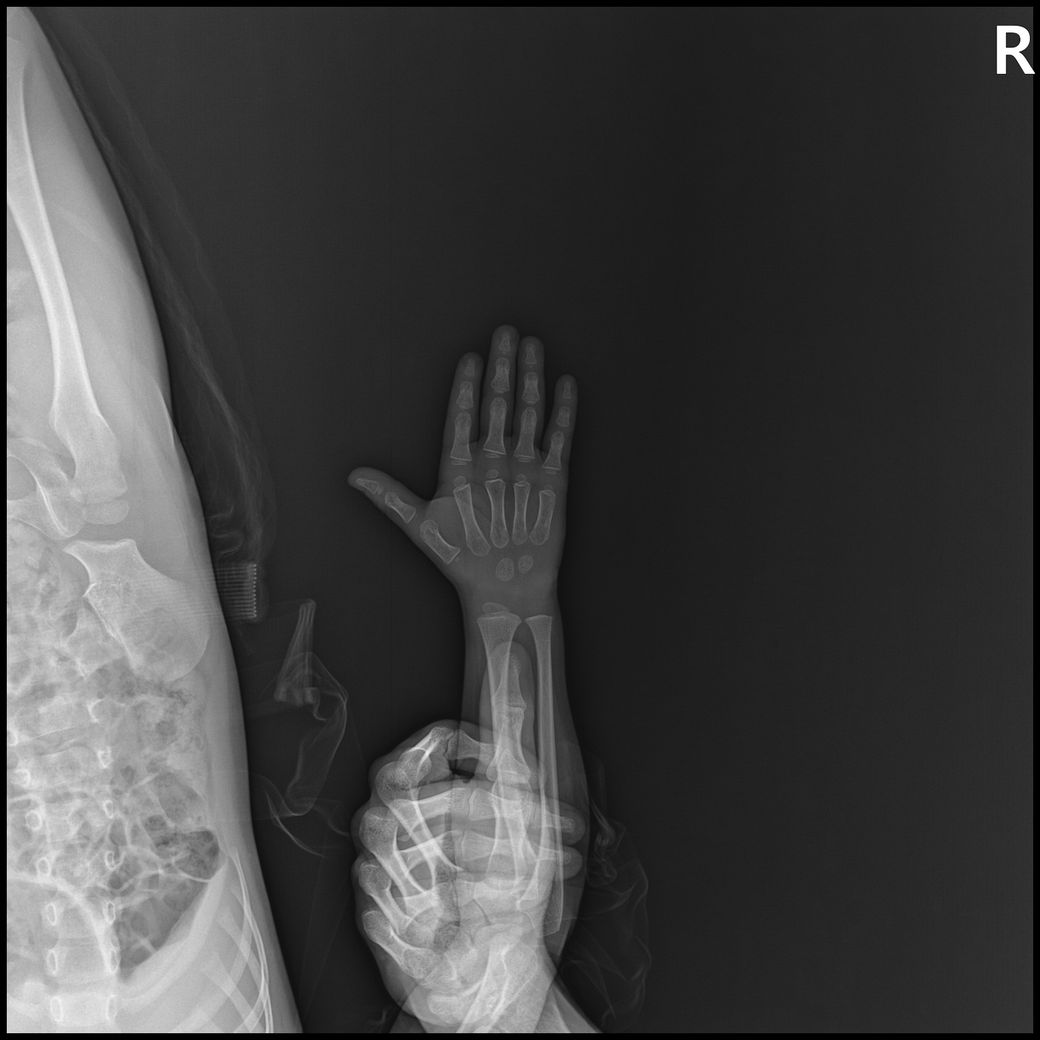

고관절,복부일부,생식기등 민감부위등이 추가로 촬영되었고

원본영상을 보니 몸통이 다찍혀서 피폭량 걱정으로 아무것도 못하고 있고

- 몸통일부+손같이찍힘 : 6장

- 손부터 팔꿈치까지 : 3장

• 4번 째 사진